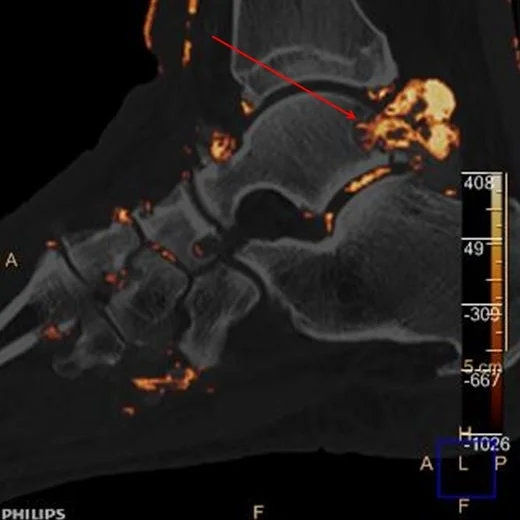

CT with uric acid overlay: Large tophus eroding into the talus (red arrow)